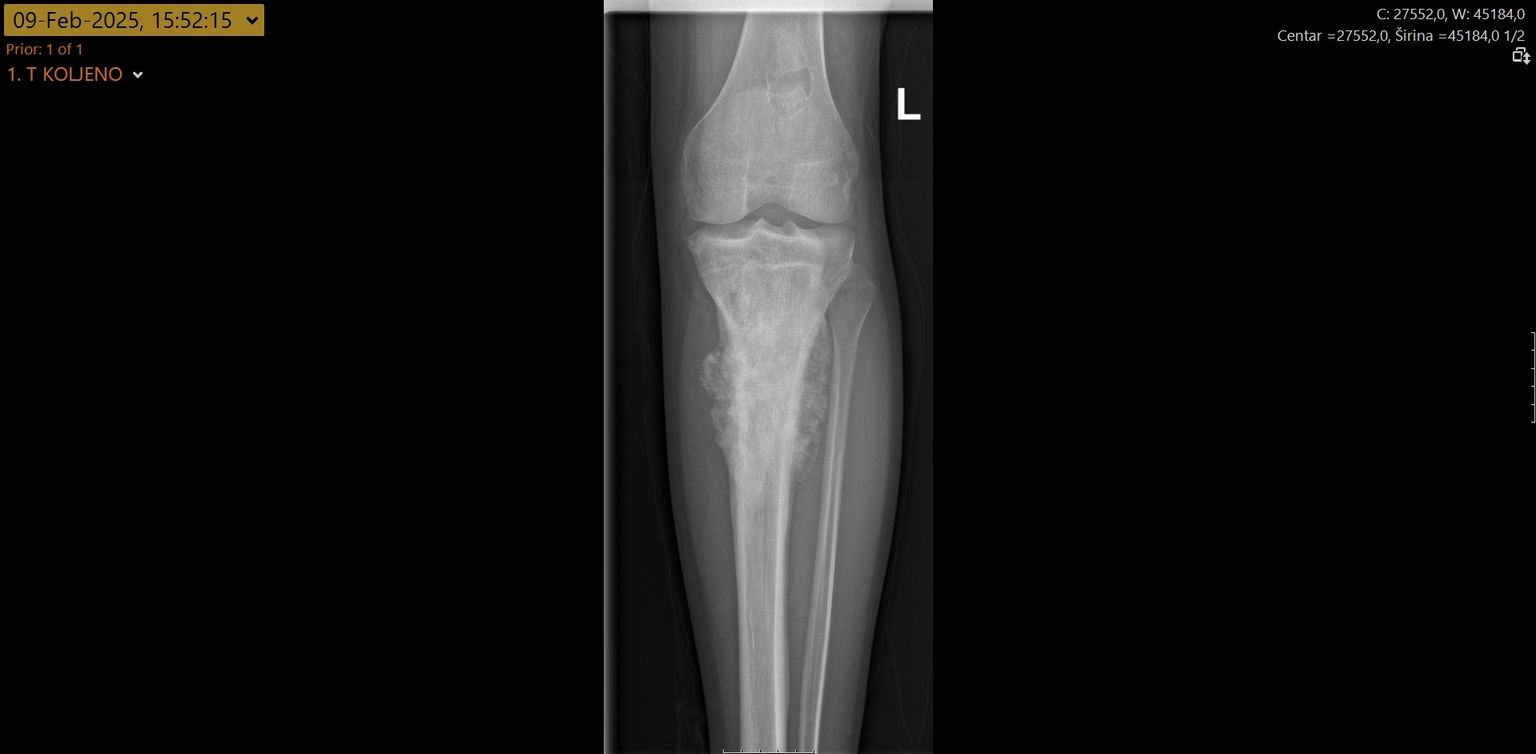

• Zahvat u KBC-u Split - 4 Foto: KBC Split

• Zahvat u KBC-u Split - 1 Foto: KBC Split